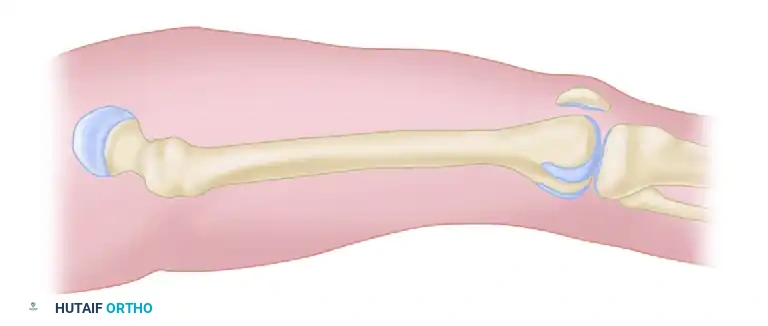

FASCIOTOMY FOR ACUTE COMPARTMENT SYNDROME OF THE THIGH

The thigh is anatomically divided into three distinct compartments: anterior, posterior, and medial. Because the thigh compartments possess a larger volume and greater compliance than those of the leg, thigh compartment syndrome is relatively rare. However, when it occurs, it is typically the result of massive blunt trauma, femur fractures, or prolonged compression.

The standard approach for thigh decompression utilizes a single extensive lateral incision to access both the anterior and posterior compartments, with a secondary medial incision reserved for specific medial compartment involvement.

Make a longitudinal lateral incision beginning just distal to the intertrochanteric line and extending distally to the lateral epicondyle of the femur. This extensive incision is mandatory to ensure complete release of the fascial envelope.